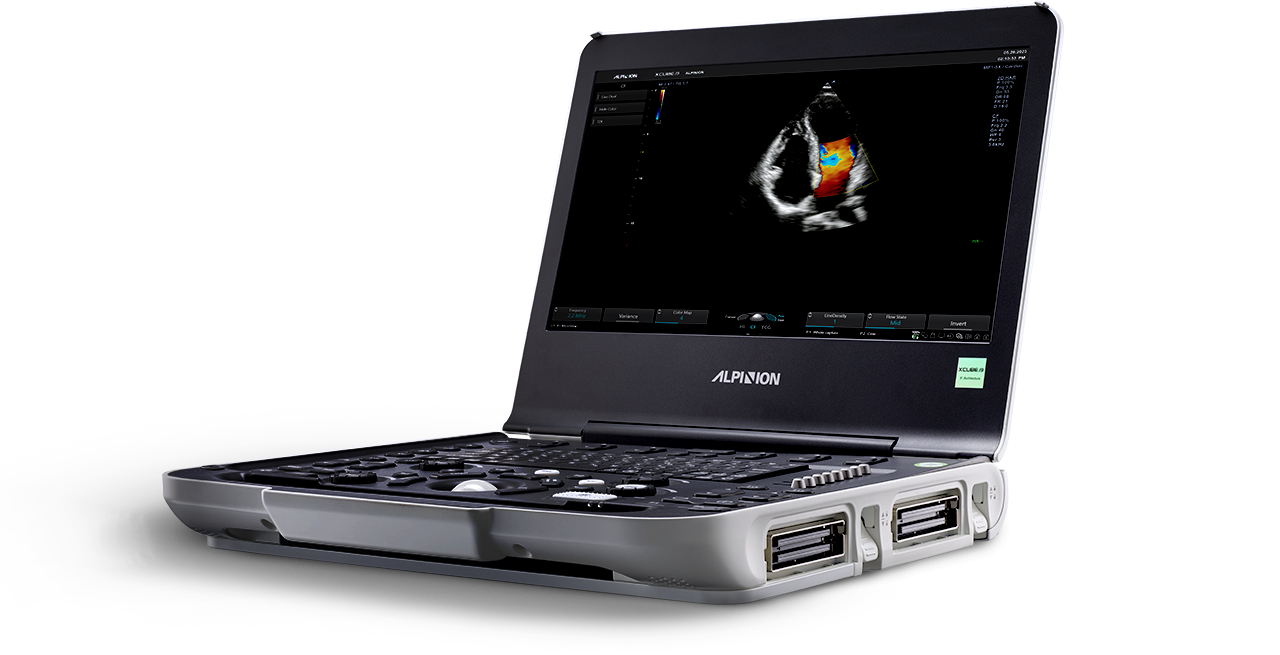

SP3-8T

Phased array transducer (3-8MHz)

Application:

Abdomen, Cardiac, EM, Pediatric

MP1-5X(NEW)

X+ Crystal Signature™ phased array (1~5MHz)

Application:

Cardiac, TCD, EM, Abdomen, Pediatric